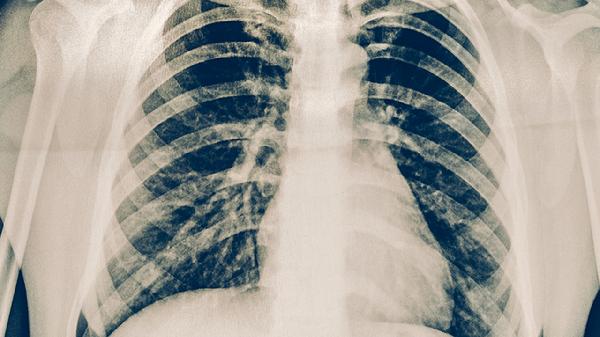

肺結(jié)核的癥狀主要有咳嗽、咳痰、咯血、胸痛、發(fā)熱等。肺結(jié)核是由結(jié)核分枝桿菌感染引起的慢性傳染病,主要通過呼吸道傳播,早期癥狀可能不明顯,隨著病情進(jìn)展癥狀逐漸加重。

咳嗽是肺結(jié)核最常見的癥狀,早期多為干咳,隨著病情發(fā)展可出現(xiàn)咳痰??人猿掷m(xù)時間較長,通常超過2周,且常規(guī)治療效果不佳。肺結(jié)核引起的咳嗽可能與結(jié)核分枝桿菌感染導(dǎo)致肺部炎癥反應(yīng)有關(guān),表現(xiàn)為刺激性咳嗽或伴有痰液排出。若咳嗽持續(xù)不緩解或加重,建議及時就醫(yī)進(jìn)行胸部影像學(xué)檢查和痰結(jié)核菌檢查。

肺結(jié)核引起的胸痛多表現(xiàn)為胸部隱痛或鈍痛,呼吸或咳嗽時疼痛可能加重。這與胸膜受累或肺部炎癥刺激有關(guān)。胸痛部位多與病變部位一致,可為單側(cè)或雙側(cè)。部分患者可伴有呼吸困難,尤其在活動后加重。胸痛癥狀提示病情可能已累及胸膜,需及時進(jìn)行胸部CT等檢查明確病情。